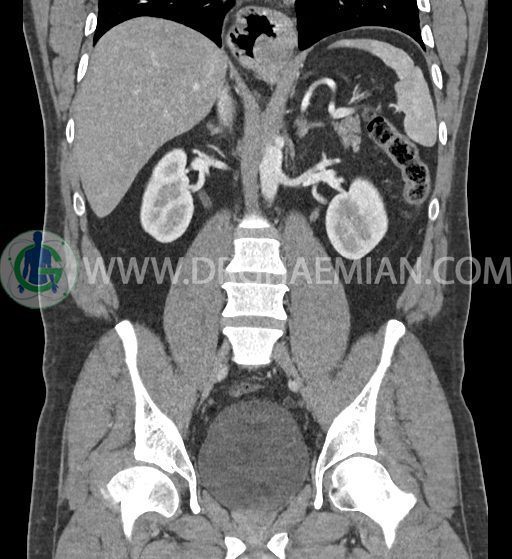

سی تی اسکن شکم و لگن با استفاده از اشعات ایکس تصاویر عرضی از ناحیه شکم و لگن ایجاد میکند. در این کیس فتق هیاتوس و هیدرویورترونفروز دیده می شود.

در سی تی اسکن اسپیرال شکم و لگن با کنتراست خوراکی و وریدی (مولتی دیدکتور 16 با مقاطع ظریف و بازسازی های ساژیتال و کرونال) :

-sliding hiatal hernia به ابعاد 60x44mm با جابجایی JE.junction و فوندوس معده به فضای مدیاستن خلفی دیده می شود.

-هیدرویورترونفروز جزئی دو طرفه دیده می شود که می تواند ثانویه به اتساع مثانه باشد.